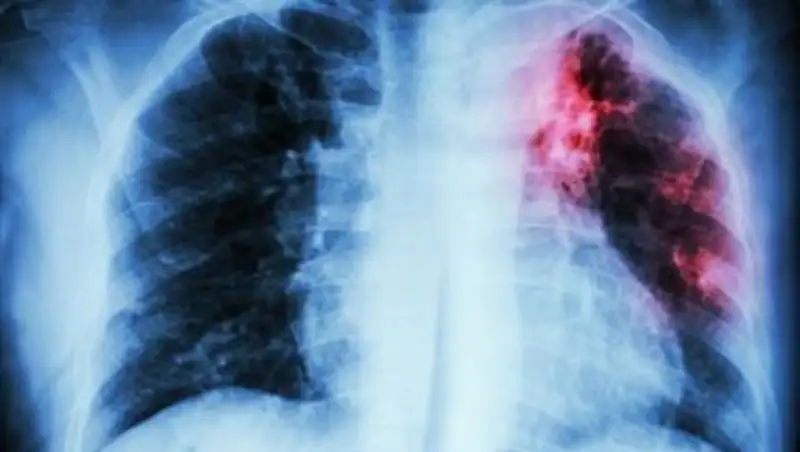

У воспитательницы детского сада в ВКО выявили туберкулез

— Информация (по заболевшей воспитательнице — прим. автора) поступила к нам в пятницу (26 января — прим. автора). Там, конечно, никакой открытой формы нет, — прокомментировал случившееся главный врач КГП на ПХВ "Центральная районная больница Зыряновского района" Владимир Коробкин. — Благодаря нашим новым аппаратам мы можем определить какие-то изменения в легких на самых-самых ранних этапах. Вот такие изменения в процессе профосмотра мы и обнаружили. Форма закрытая.

В целях профилактики действительно детей отправят сдавать анализы, проходить рентген и делать пробы Манту. Но такие меры будут предприняты только для воспитанников той группы, в которой работала заболевшая сотрудница детсада.